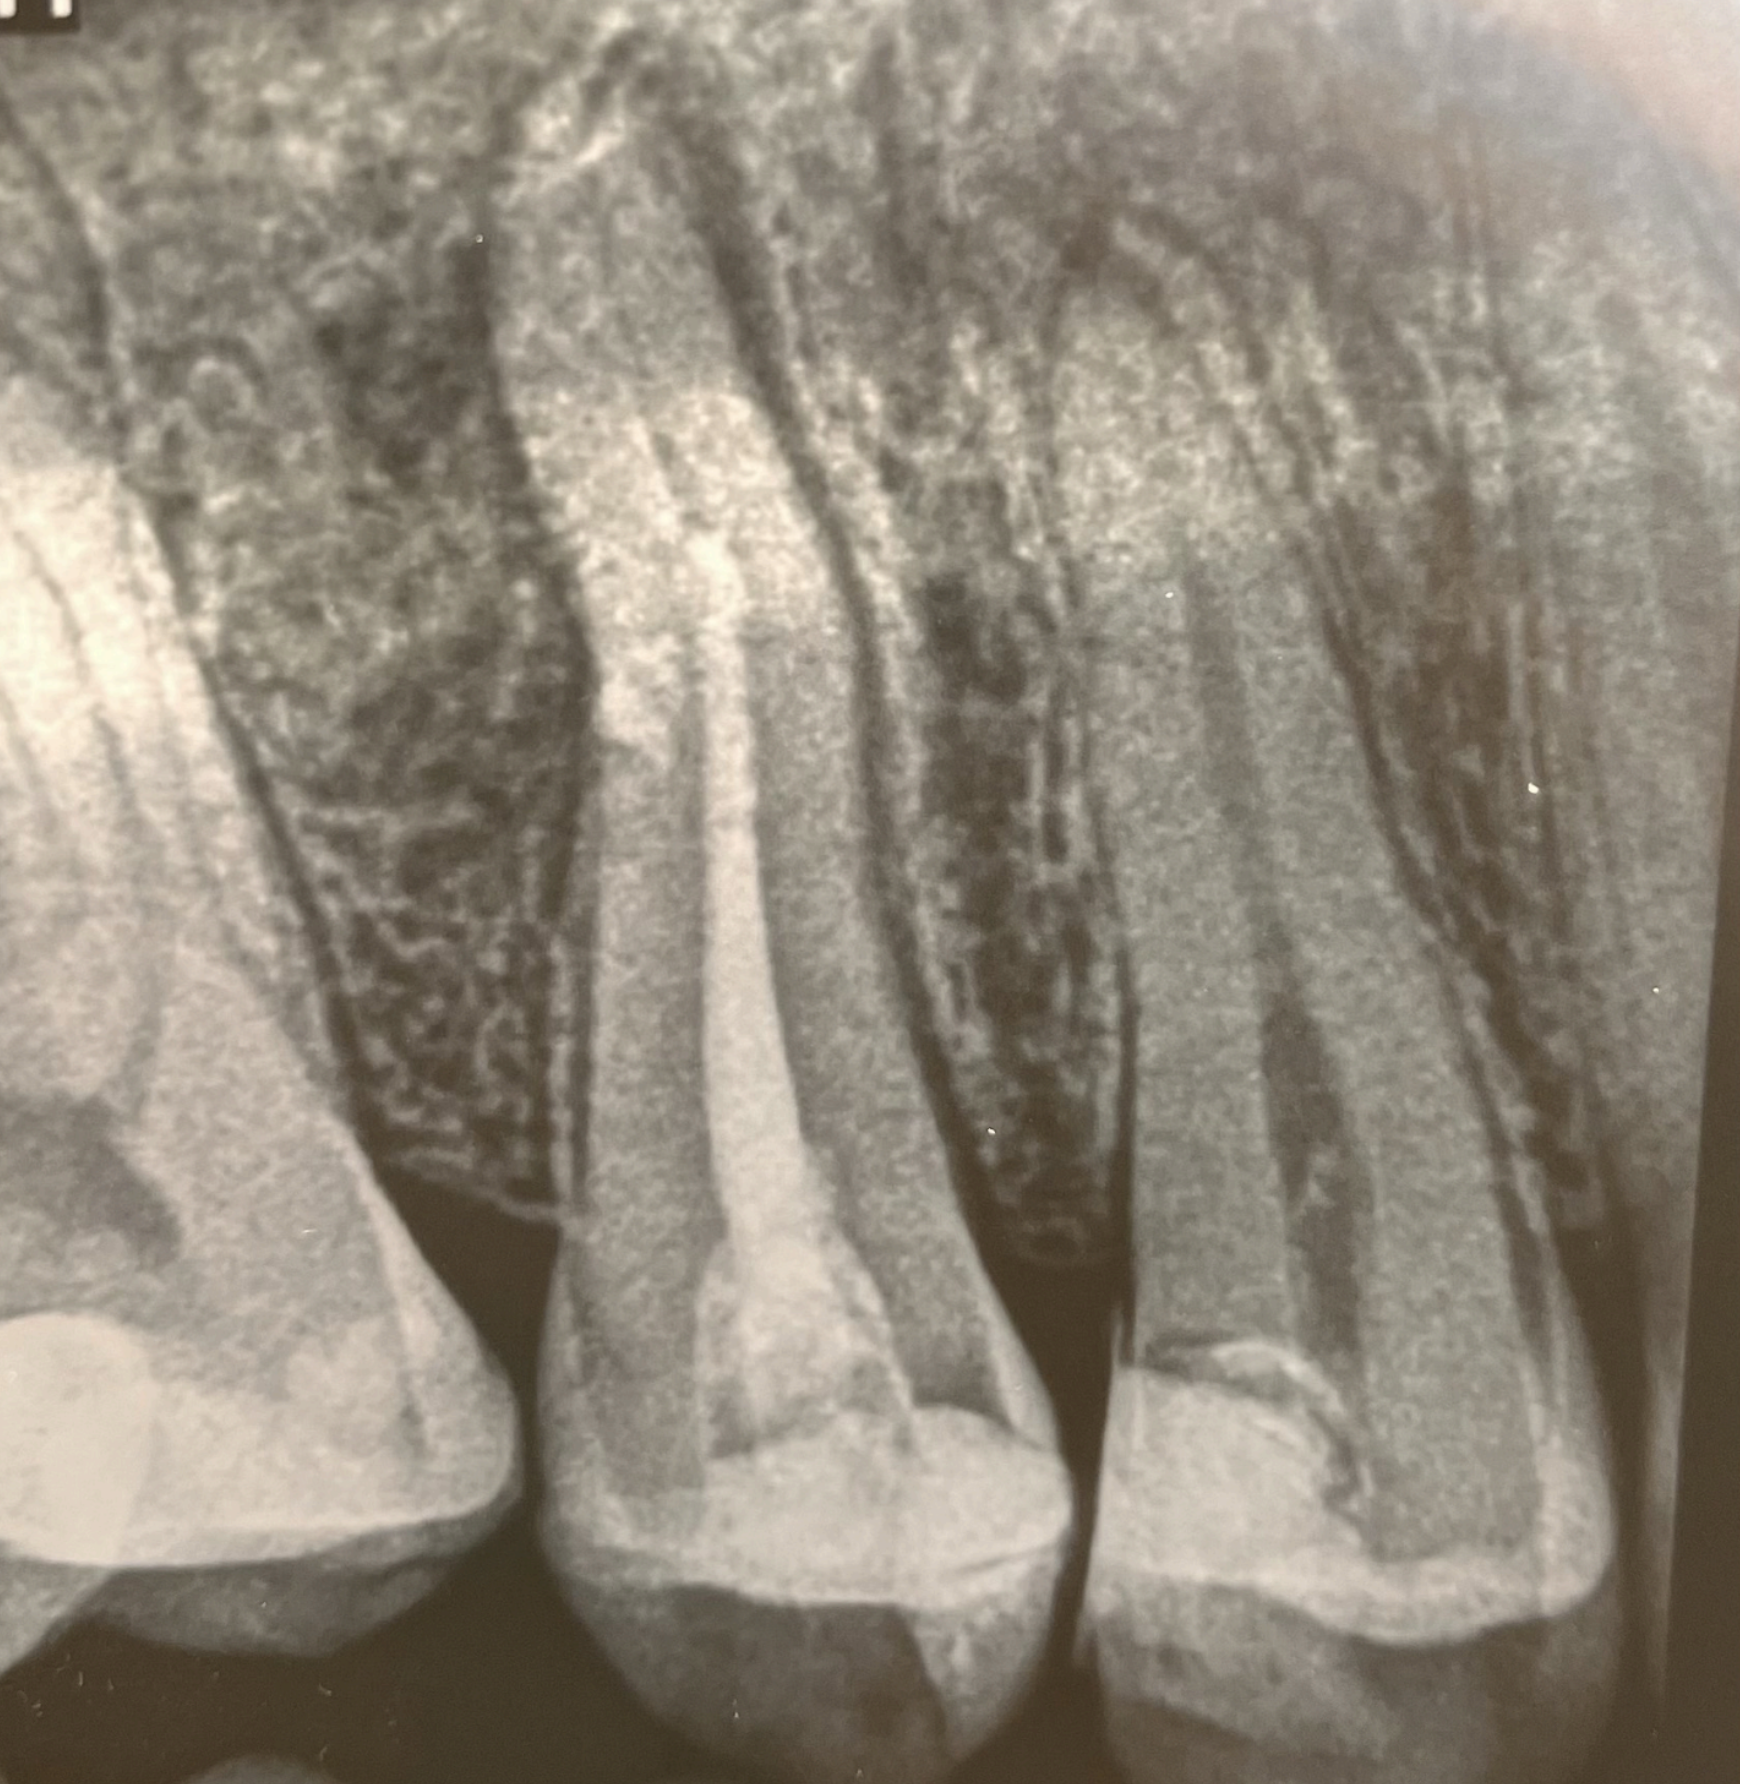

In acest caz, ne confruntam cu un tratament endodontic realizat in trecut, care nu a reusit sa sigileze intregul sistem endodontic, astfel ca pacientul se prezinta cu durere la masticatie in zona premolarului 2 superior.

In cazul pacientului nostru, tratamentul de canal initial poate fi judecat prin prisma faptului ca “linia alba din centrul dintelui” nu ajunge pana la varful radacinii, iar probabil din aceasta cauza se poate observa si o zona neagra (radiotransparenta) la varful racadicii care semnifica o infectie – de unde si durerea la masticatie.

Uneori, chiar daca radiografia indica un tratament de canal aparent corect, durerea poate sa reapara si un retratament sa fie din nou indicat. In aceste cazuri, etiologia este mai complexa, fiind uneori vorba despre un canal in plus netratat, o fisura/fractura a dintelui sau o leziune parodontala.